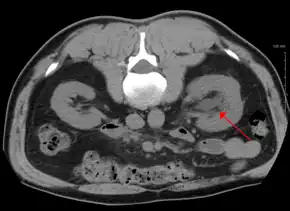

Hydronephrosis due to a kidney stone at the ureteral vesicular junction seen on CT scan

The choice of imaging depends on the clinical presentation (history, symptoms and examination findings). In the case of renal colic (one sided loin pain usually accompanied by a trace of blood in the urine) the initial investigation is usually a spiral or helical CT scan. This has the advantage of showing whether there is any obstruction of flow of urine causing hydronephrosis as well as demonstrating the function of the other kidney. Many stones are not visible on plain X-ray or IVU but 99% of stones are visible on CT and therefore CT is becoming a common choice of initial investigation. CT is not used however, when there is a reason to avoid radiation exposure, e.g. in pregnancy.